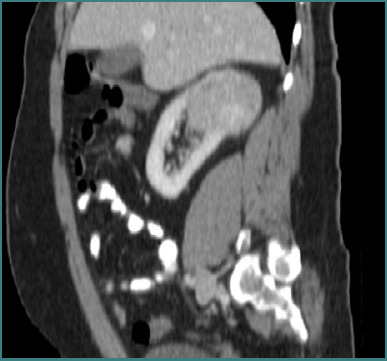

We report the case of a 58-year-old male with metachronous renal tumors and a solitary kidney who had previously undergone an open right radical nephrectomy with extended lymphadenectomy for an invasive renal cell carcinoma (RCC) (pT3a N0M0) in November 2013. In May 2022, during routine surveillance, a left lower pole lesion measuring 2.5 × 2 × 1.6 cm was detected, and the patient was submitted to robot-assisted partial nephrectomy (RAPN). The histopathological study confirmed the presence of a pT1a Fuhrman grade 3 clear cell renal carcinoma. In October 2024, follow-up imaging revealed a new upper pole lesion measuring 4 × 3 × 2.3 cm in the left kidney. The patient was submitted to a novel robot-assisted partial nephrectomy, which was successfully completed using selective clamping of the renal artery. The clamping time was 28 minutes (versus 17 minutes during the initial procedure), and the estimated blood loss increased to approximately 300 mL compared to about 100 mL previously, with a console time of 98 minutes. The patient was discharged after the second surgery in good functional status. The final pathology revealed clear cell RCC, Fuhrman grade 2/nucleolar grade 2 (WHO/ISUP 2016), and pT1a, with negative margins. Despite increased technical challenges during reoperation, postoperative renal function remained stable, underscoring the feasibility of repeat RAPN in a solitary kidney.

Abstract Image